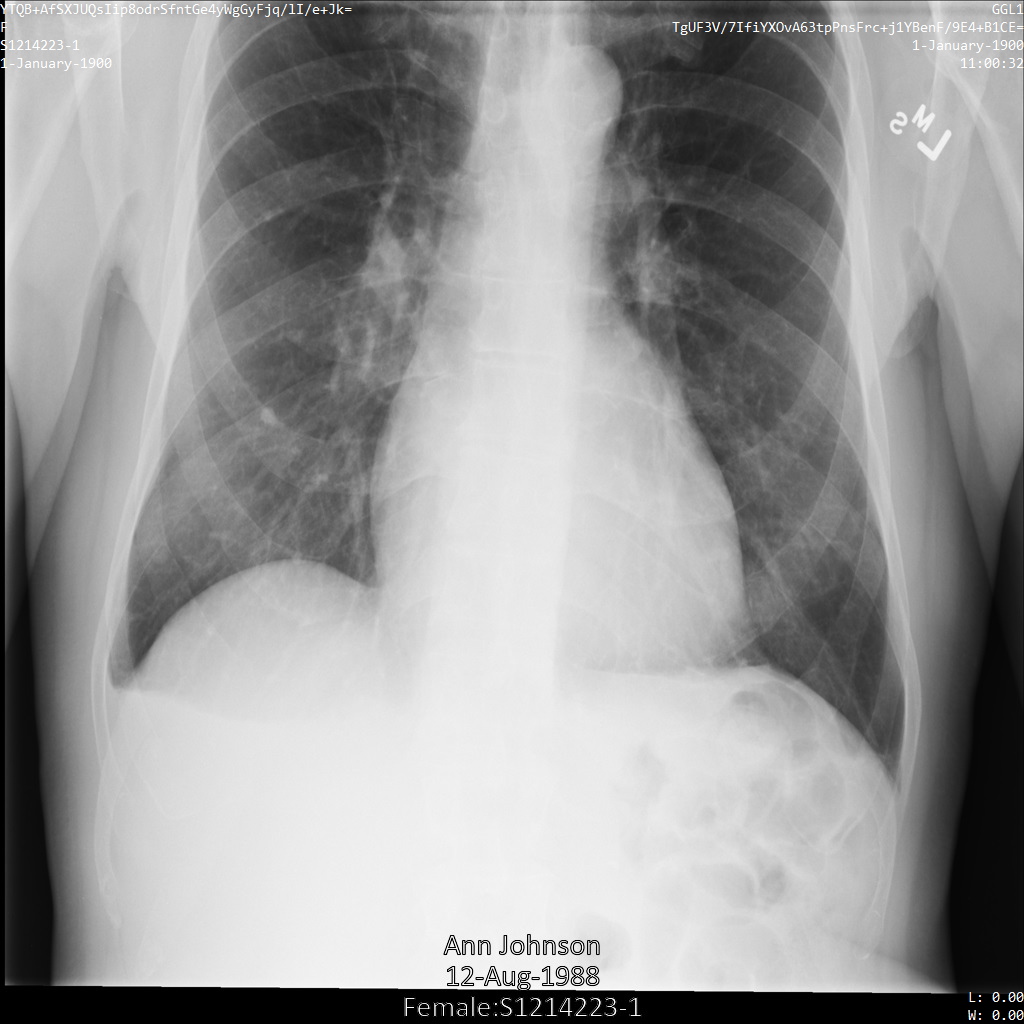

Después de enviar la imagen a la API Cloud Healthcare mediante las opciones REDACT_ALL_TEXT y DEIDENTIFY_TAG_CONTENTS, la imagen aparece de la siguiente manera. Observa los siguientes cambios:

- Los nombres de las esquinas superior izquierda y superior derecha de la imagen se han transformado

con una

CryptoHashConfig. - Las fechas de las esquinas superior izquierda y superior derecha de la imagen se han transformado

DateShiftConfig. - El texto insertado en la parte inferior de la imagen se oculta

Después de enviar la imagen a la API Cloud Healthcare mediante el perfil DEIDENTIFY_TAG_CONTENTS, la imagen se muestra de la siguiente manera.

Observa los siguientes cambios:

DateShiftConfig.